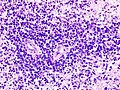

Microscopic

Features:

- Large cell lymphoma.

- Size = 2x diameter normal lymphocyte.

- Nucleolus - common.

- Perivascular clustering.

Images